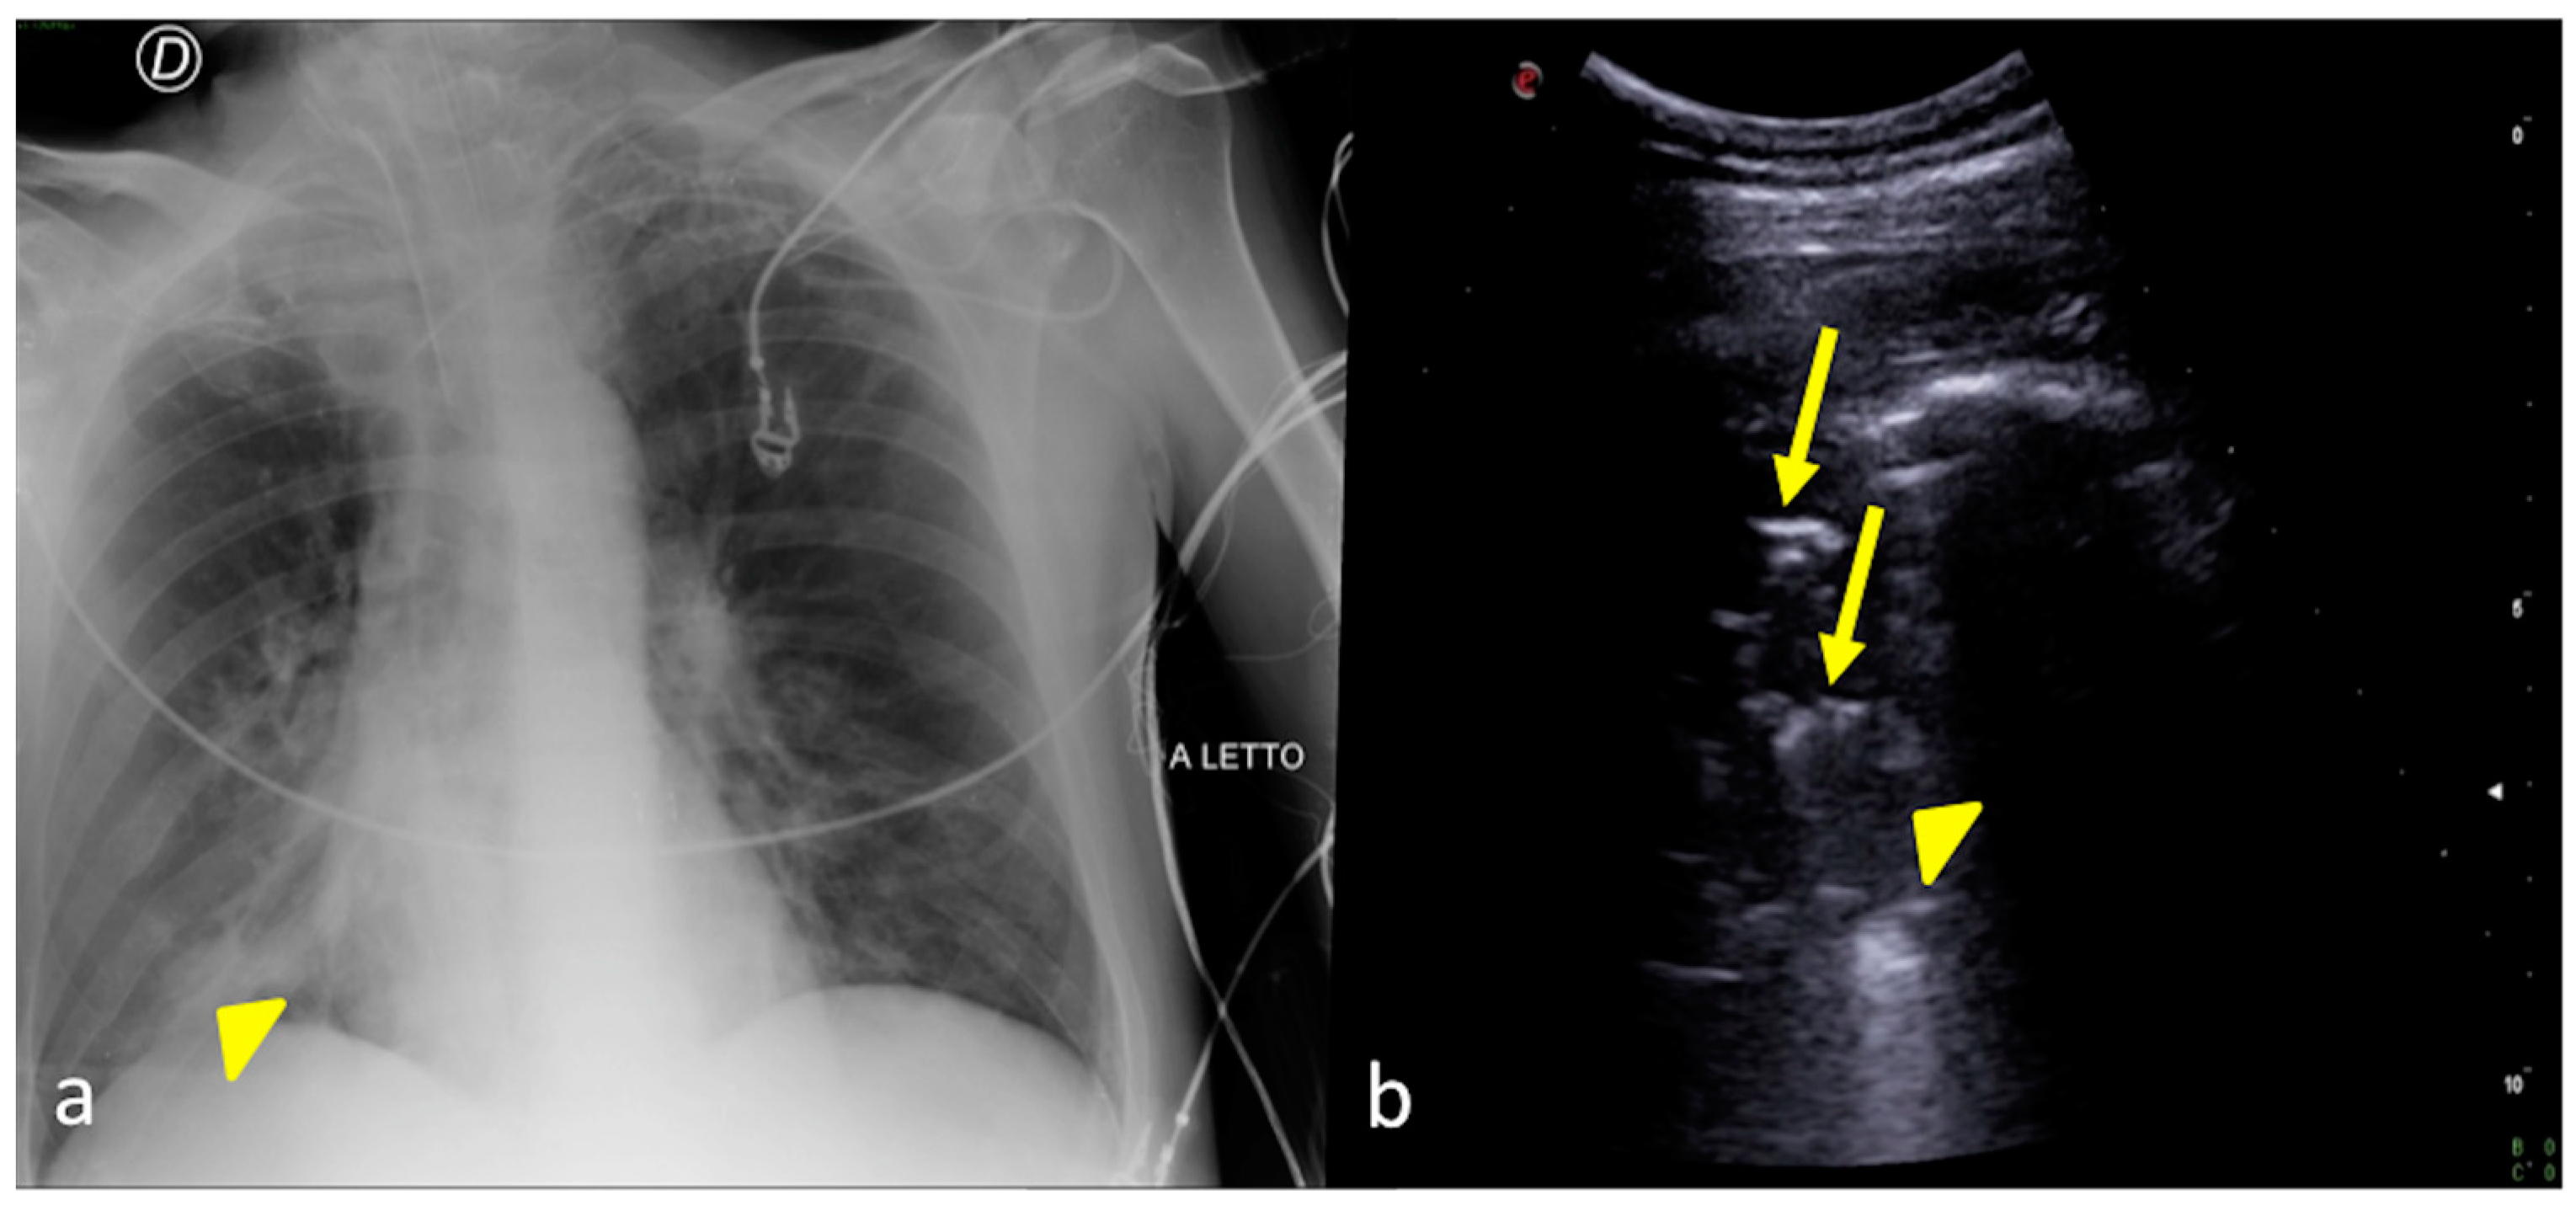

2.3. Pleural Effusion